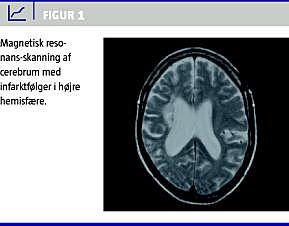

Patienten blev overflyttet til Neurologisk Afdeling for at udelukke anden organisk sygdom. Klinisk fandtes ingen tegn på ny apopleksi og computertomografier var uden tegn på nye infarkter. Elektroencefalogram (EEG) udelukkede nonkonvulsiv status epilepticus. Forløbet blev kompliceret af pneumoni, som responderede på antibiotika. Da Psykiatrisk Afdeling fortsat fandt tilstanden uforklaret, blev der suppleret med magnetisk resonans-skanning af cerebrum, der bekræftede de computertomografiske fund (Figur 1 ). Lumbalpunktur udelukkede encephalitis og kontrol-EEG var normalt.